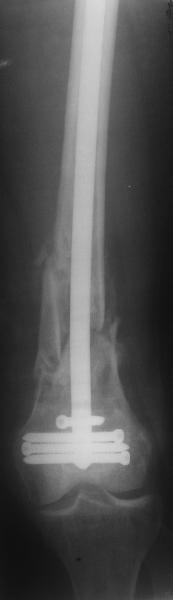

Результат операции блокирующего остеосинтеза многооскольчатого перелома бедра. Применены винты собственной конструкции.(моделирование спогиозного винта)

По прямой проекции неплохо. Что за стержень?

Примеры приложены.

И вообще мне кажется, что представленный ОС не допустим:1. стержень в суставе,2. неправильная длинна винтов, 3. ось конечности неправильная, 4. циркулярная гипсовая повязка после ОС?????

Приносим извенения за недостаток информации. Выкладываю все снимки. Стержень фирмы НПО ДЕОСТ(г.Пущино-на-оке)